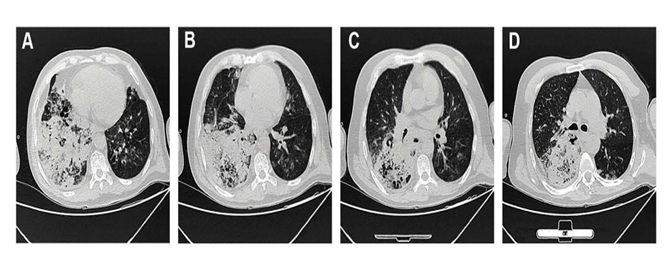

社区获得性铜绿假单胞菌肺炎

影,内部有坏死和小空洞提示为化脓性炎,后来确诊为铜绿假单胞菌肺炎